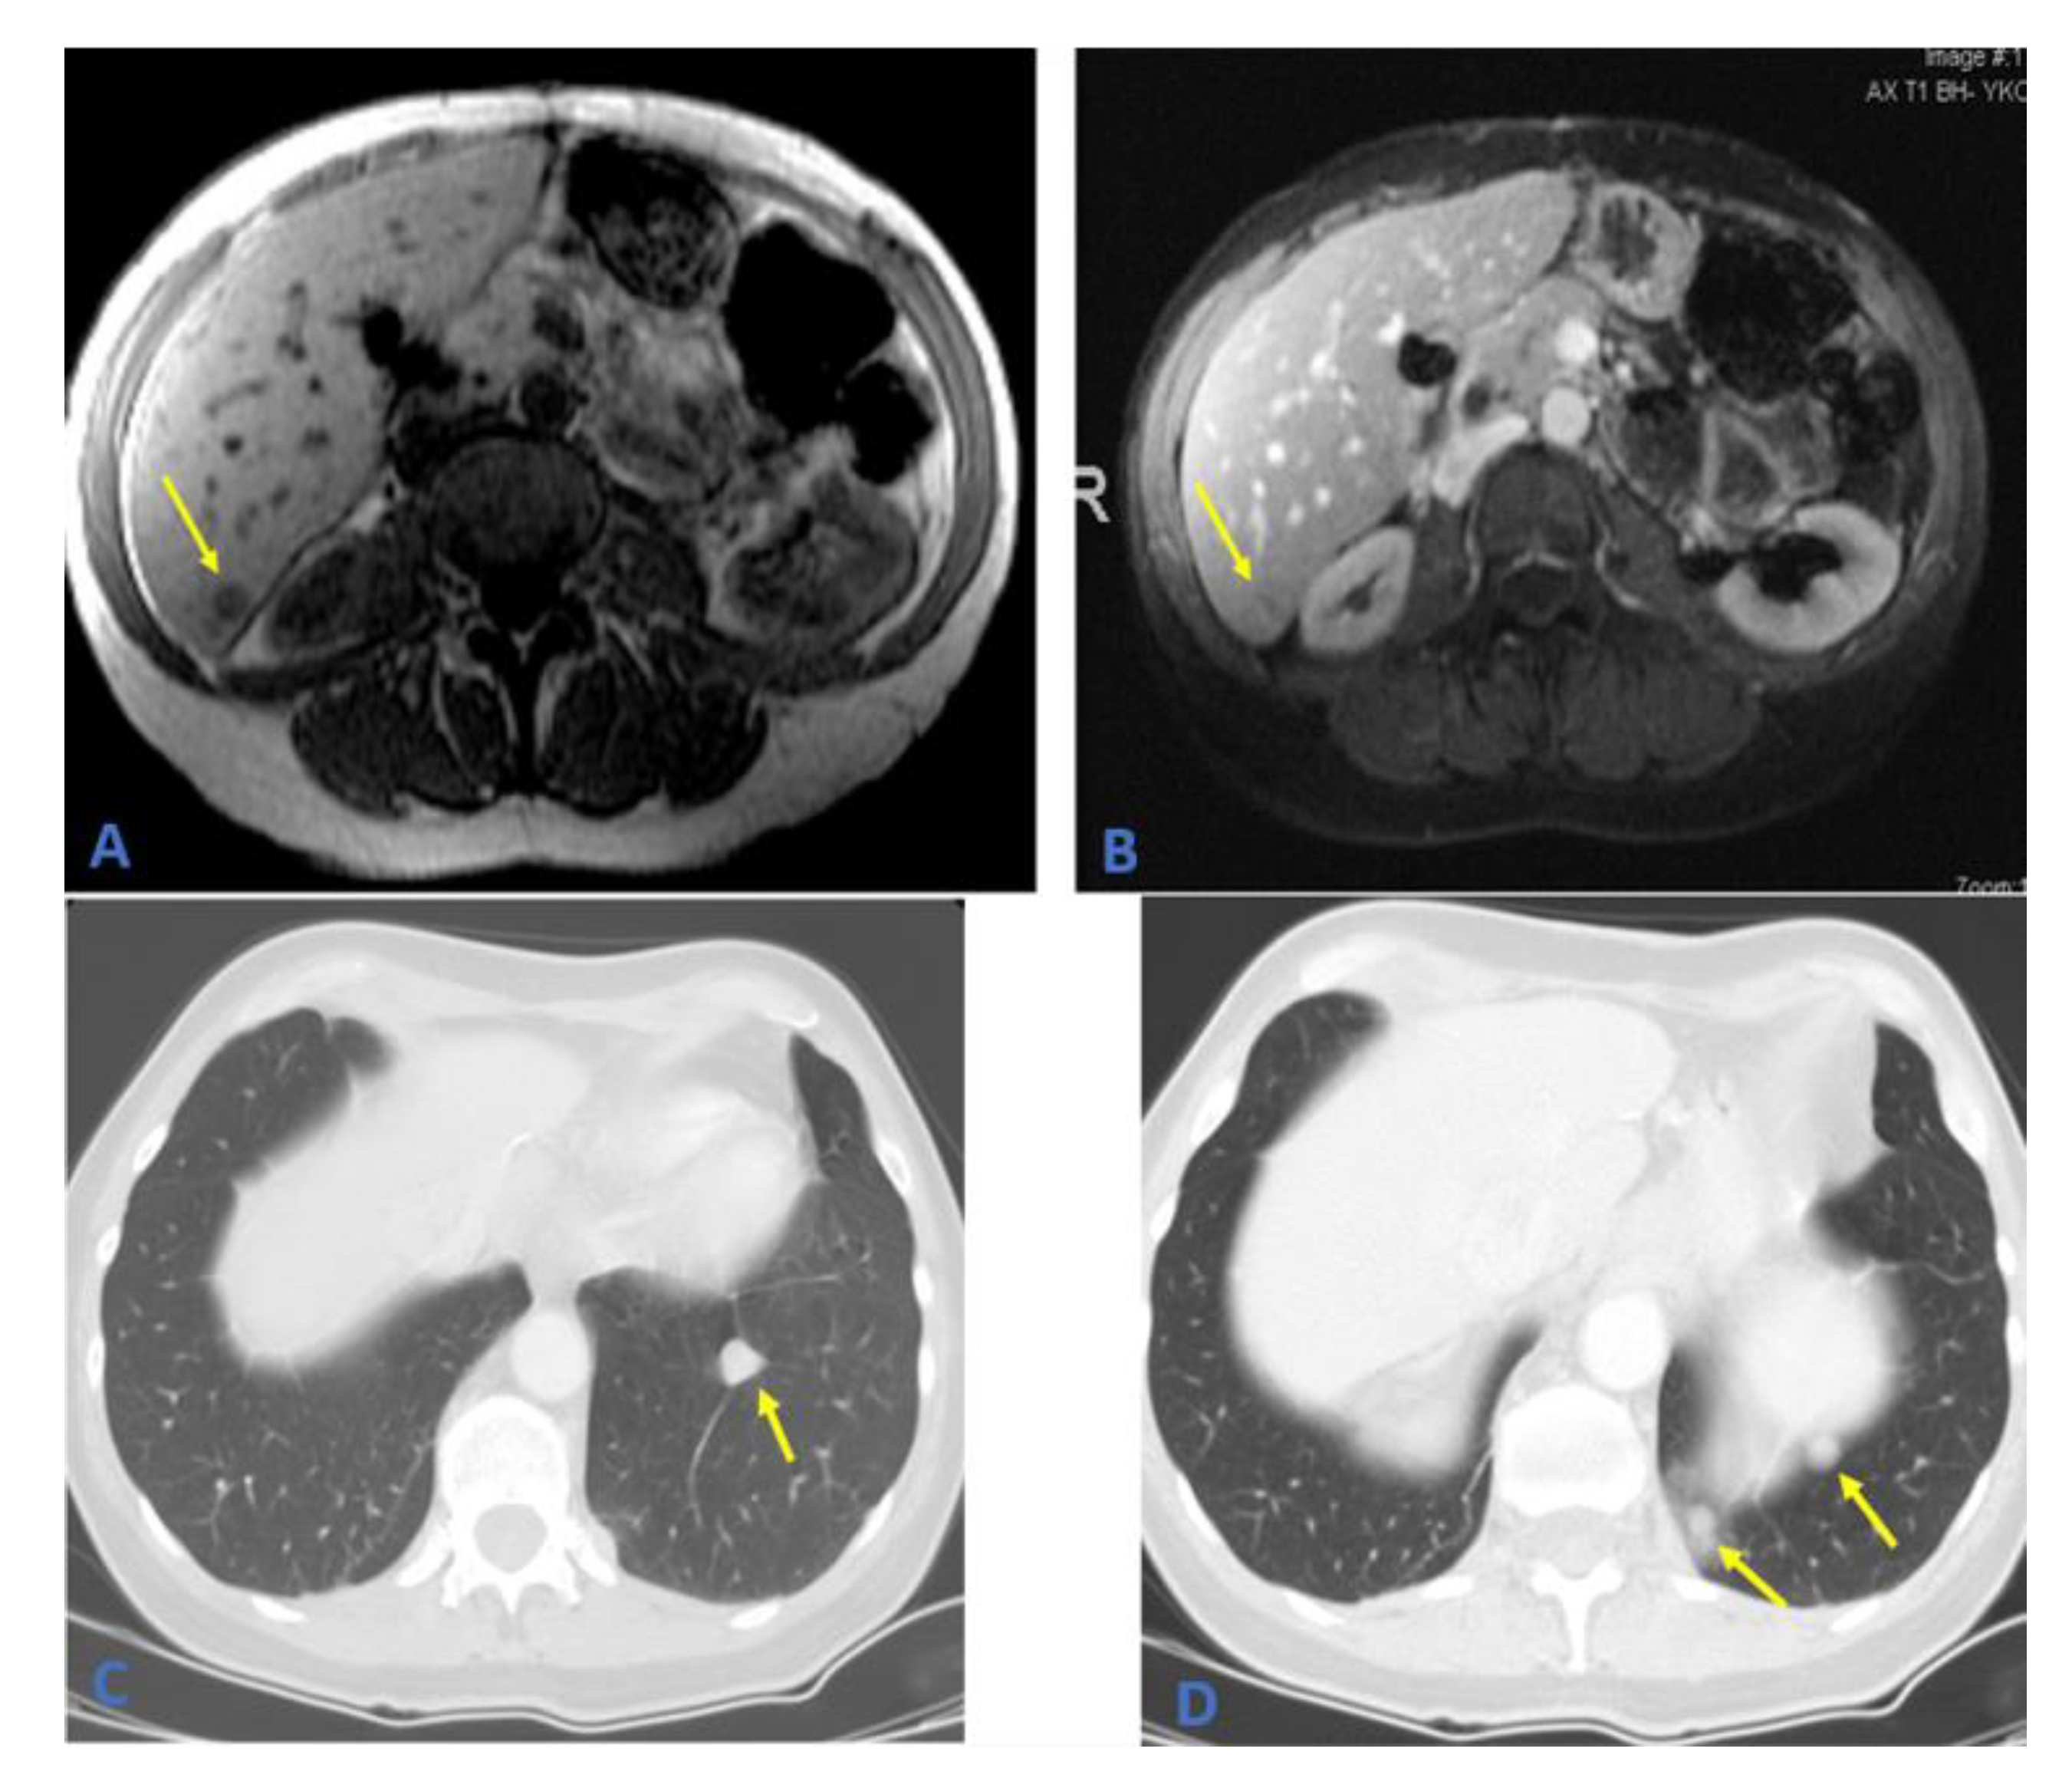

2. Case Presentation